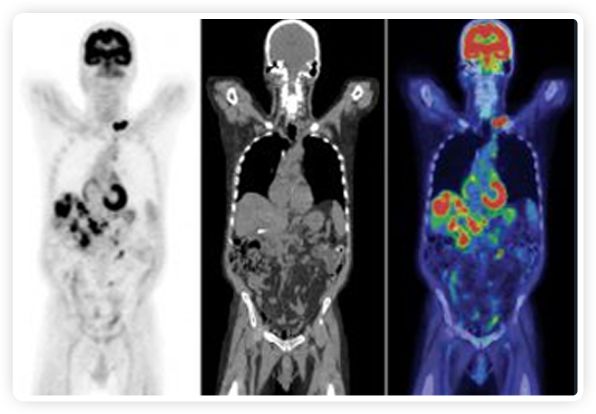

PET+放療共同治療

RefleXion將PET成像與立體定向放射治療相結(jié)合。在注射示蹤劑后,RefleXion的技術(shù)基于示蹤劑信號實(shí)時地在一個或多個目標(biāo)上引導(dǎo)治療性X射線。使用這種專有方法,RefleXion的平臺有可能比現(xiàn)有系統(tǒng)向癌癥病變提供更高劑量的輻射,并改善周圍健康組織的保護(hù)。

為了避免PET長圖像采集時間,RefleXion開發(fā)了一項(xiàng)專利技術(shù)使用重合的PET光子對來指導(dǎo)放射治療束,因?yàn)閷?shí)時檢測發(fā)射的光子,為生物指導(dǎo)提供了一種時間有效的方法。